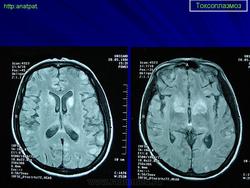

Токсоплазмоз

Церебральный токсоплазмоз.

Церебральный токсоплазмоз

Neurotoxoplasmosis